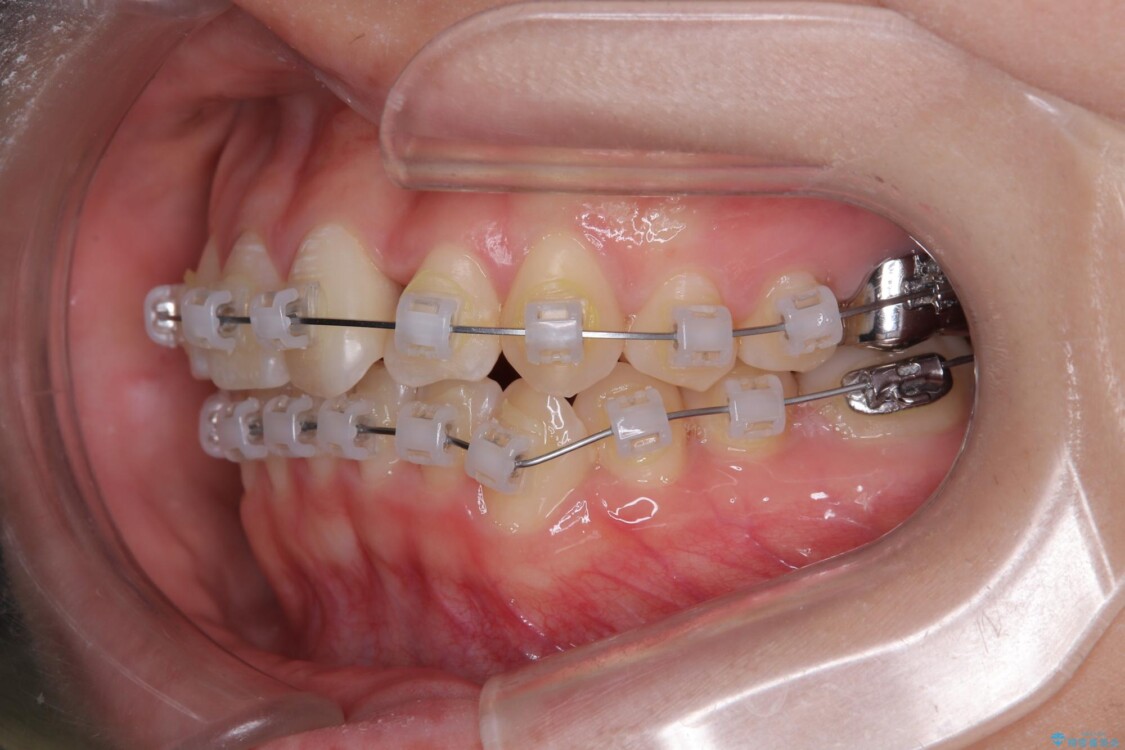

治療途中

• 前歯のねじれ・ガタガタを10か月で改善!20代女性の矯正治療|クリアブラケットでむし歯になりにくい歯並びへ改善 治療途中画像

診察の結果、上下の前歯部に**叢生(そうせい/歯のガタガタ・重なり)**が認められました。

特に上の前歯にはねじれや重なりがあり、審美的にも清掃性にも影響している状態でした。

治療方法としては、装置の目立ちにくさと費用面のバランスを考慮して、プラスチック製のクリアブラケットとメタルワイヤーを組み合わせた矯正装置を使用することにしました。